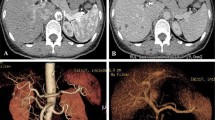

The CNR values for the liver, abdominal aorta and portal vein on monochromatic images in the range of 40–60 keV in protocol B were all significantly higher than those in protocol A (P < 0.001 for each comparison) except for the liver in AP (P = 0.127, 0.307, 0.121 for 40–60 keV, respectively) (Figs. 2 and 3), an average increase of 44–67 % in AP and 50–94 % in PVP, respectively. However, there were no significant differences in CNR of any ROI between protocol B at 70 keV and protocol A, except for the liver in PVP (P = 0.017) (Fig 2, Table 3).

Transverse contrast-enhanced conventional CT images (a for AP, f for PVP) with 120 kVp, 90 mL contrast agent and FBP in a 57-year-old man with BMI of 25.71 kg/m2 and monochromatic images (b-e for AP and g-j for PVP) with spectral imaging, 43 mL contrast agent and ASIR in a 55-year-old man with BMI of 24.44 kg/m2. The overall image qualities for the images at 120 kVp were similar to that at 40 keV, lower than those at 50 keV and 60 keV, and higher than that at 70 keV